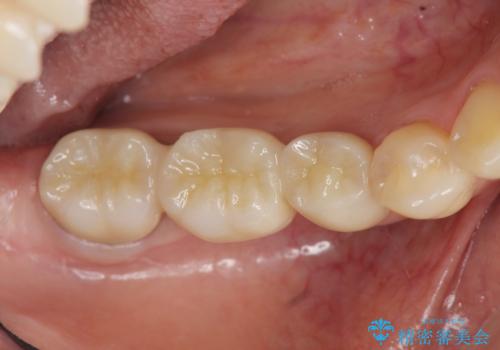

セラミックブリッジによる審美・咬合機能回復治療

- 銀歯が取れてしまい、治療を希望され来院されました。

歯には大きな穴が開き、虫歯も大きくなってしまい残すことが難しいような状況であったため抜歯を余儀なくされました。

抜歯後はセラミックブリッジを用いた咬合機能回復を計画します。

- 24万円(仮歯・フルジルコニアクラウン×3)費用は治療当時の料金となります